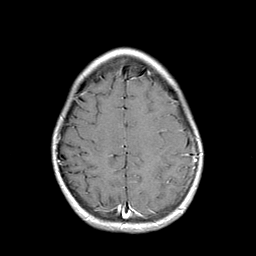

Metastatic bronchogenic carcinoma: T1-weighted MR -- Slice #18

[Home][Help][Clinical] Slice 18